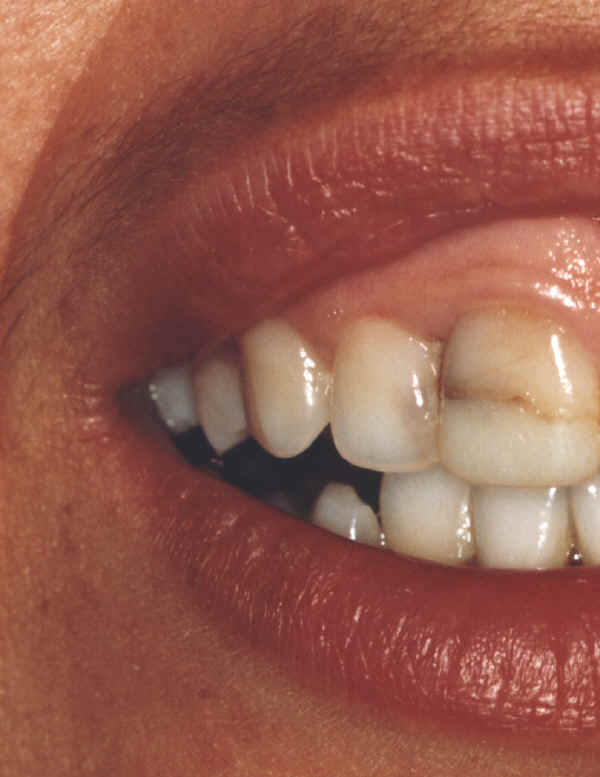

Os autores exemplificam, neste trabalho, de forma gráfica, a possibilidade de

adulteração de imagens digitais, obtendo "clones" com características

completamente diversas, quase sem possibilidade de se definir qual delas é a original.

Diversos recursos de edição computadorizada de imagens, que permitem alterações

imperceptíveis na impressão ou visualização em monitor, são demonstrados. Imagens com

grande resolução podem ser periciadas, comprovando-se eventuais adulterações.

Qual destas imagens não foi editada?

Qual destes lados não foi editado?

Responda, justificando, e receba a resposta com as fotos originais!

Matematicamente a probabilidade de erro na 1ª resposta é igual a 75% = 3/4 x 100

Matematicamente a probabilidade de erro na 2ª resposta é igual a 50% = 1/2 x 100

Não aposte sua prova jurídica nisto, responda e verás!